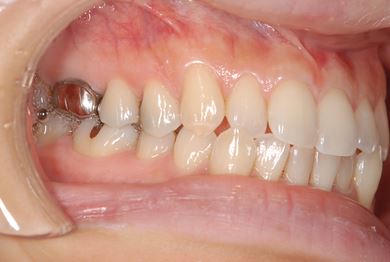

| 性別/年齢 | 女性 / 34歳 | ||||||||||||||||||||||||||||||||

| 主訴 | 以前虫歯を治療して金属を入れたところが、再び虫歯になったのか、軽くしみたり違和感がある。 | ||||||||||||||||||||||||||||||||

| 治療方針 | セラミック治療にて、審美的回復を行う。 | ||||||||||||||||||||||||||||||||

| 治療内容 | メタルボンドセラミッククラウン1本(メタルボンド用土台1本) | ||||||||||||||||||||||||||||||||

| 総治療費 | 125,685円 | ||||||||||||||||||||||||||||||||

| 治療期間 | 3ヶ月 |